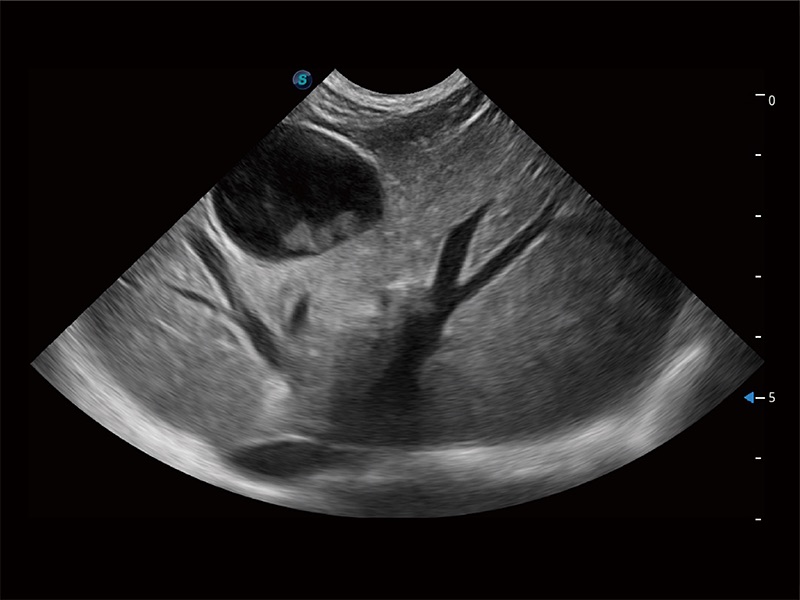

动物是人类最亲密的朋友和最值得信赖的伙伴。云顶集团官网也一直致力于探索动物专用的超声影像解决方案。全新推出的ProPet系列,是云顶集团官网在动物超声影像智能化、专业化、精准化的一次跨越式革新。动物不能用言语来表述自己的不适,通过超声影像,ProPet系列搭建了动物医生与不同物种沟通的“桥梁”,为动物医生注入了“治愈之力”。 ProPet 80 是云顶集团官网匠心打造的一款高端动物专用彩超,采用性能卓越的全新硬件架构,极大提升超声系统的运行效率和数据处理能力,帮助动物医生从容应对日益增多的挑战性病例和日益多样化的临床需求。

高性能和先进的临床应用工具可以为动物医生提供临床信心。ProPet 80 搭载了先进的腹部和浅表应用工具,帮助医生在日常临床实践中发挥前所未有的作用。

ProPet 80 全新的动物超声智能软件和丰富的探头群,为动物医生提供了高清晰度和精细分辨率的图像,无论在宠物、马科、畜牧还是实验室动物等应用中都可以轻松应对,为您的日常工作带来满意的体验。